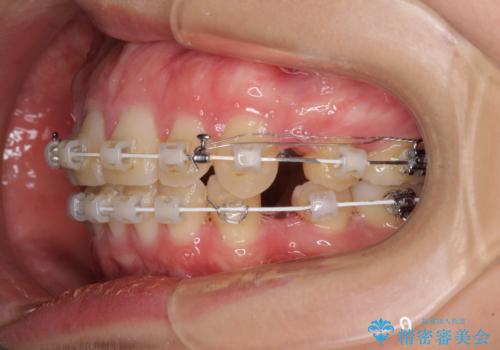

上顎前突 目立たないワイヤー装置での抜歯矯正

- 口元の突出感改善を希望して来院された患者様です。

口元を積極的に引っ込めるために、上下左右の小臼歯計4本を抜歯することとしました。

咬み合わせが深いため、咬み合わせの高さを向上させながら口元を下げることとしました。

左右ともに下顎に対して上顎歯列が前方位にある上顎前突であったので、上顎歯列全体を後方に移動させることで上下咬み合わせを改善し、その上で抜歯矯正により口元の突出感を改善させていきました。